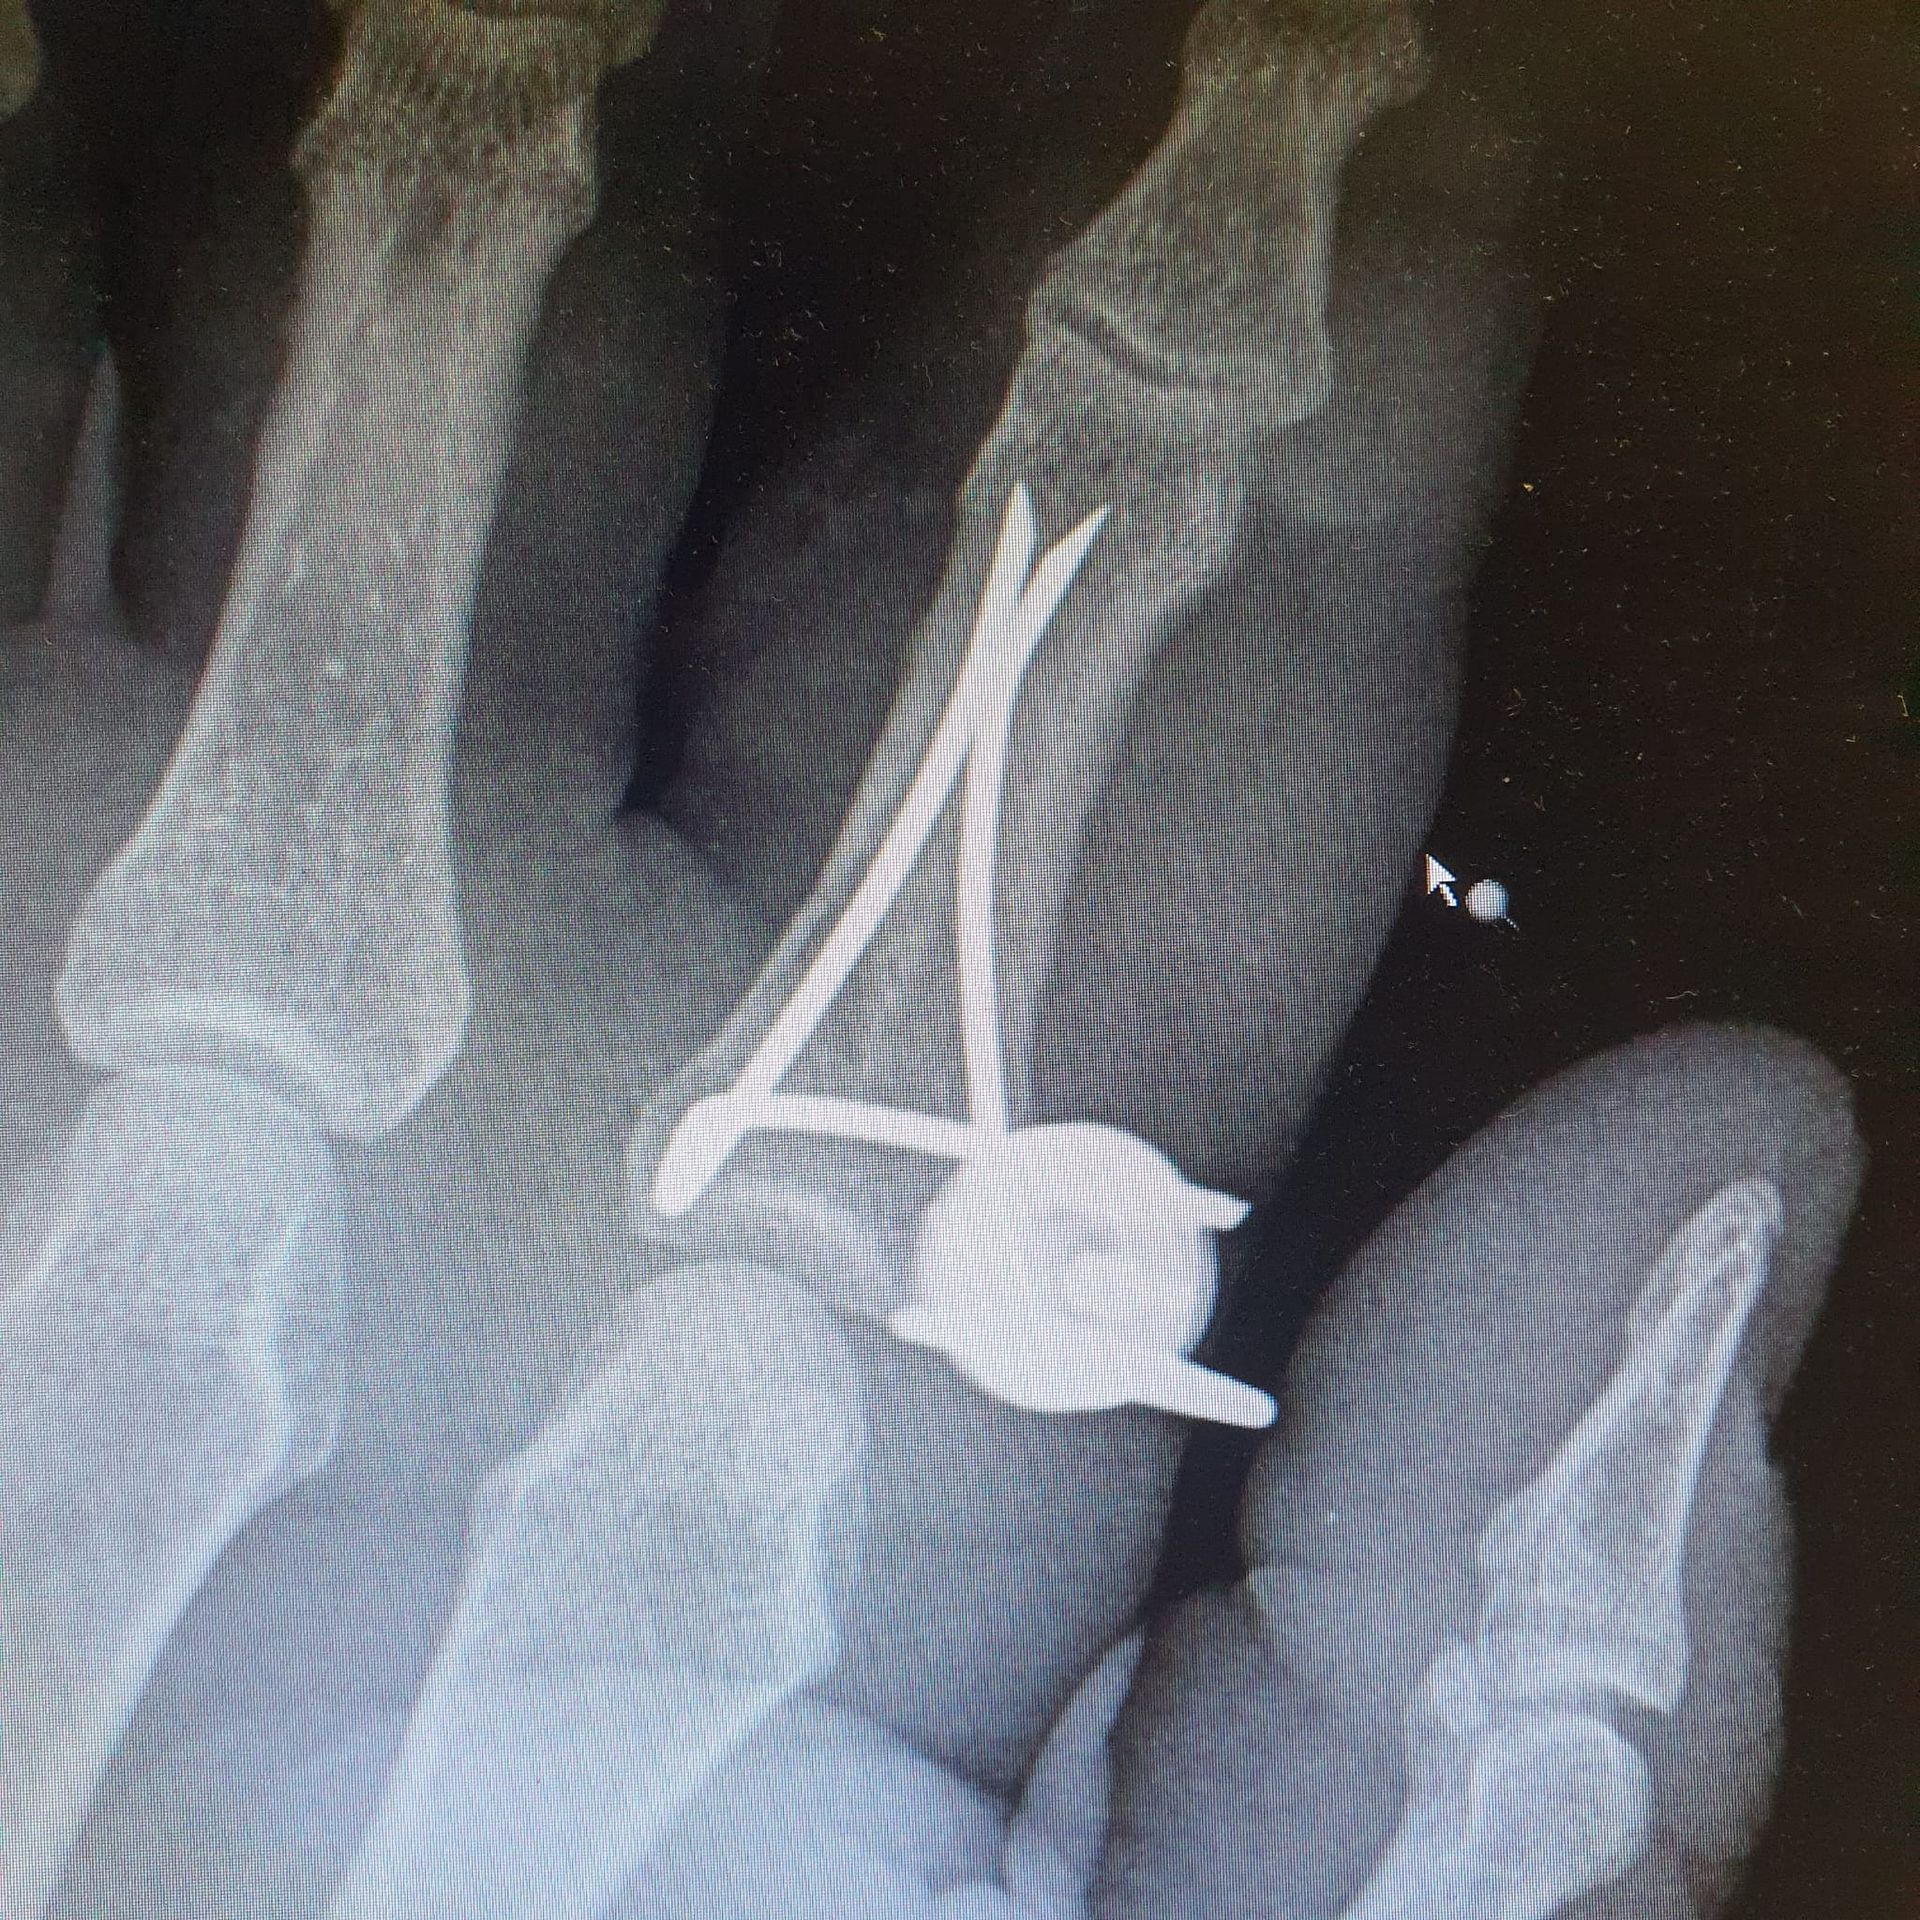

I NOSTRI INTERVENi

Dispositivi Technovare in sala

Radiografie di interventi realizzati con i nostri dispositivi in strutture pubbliche e private.